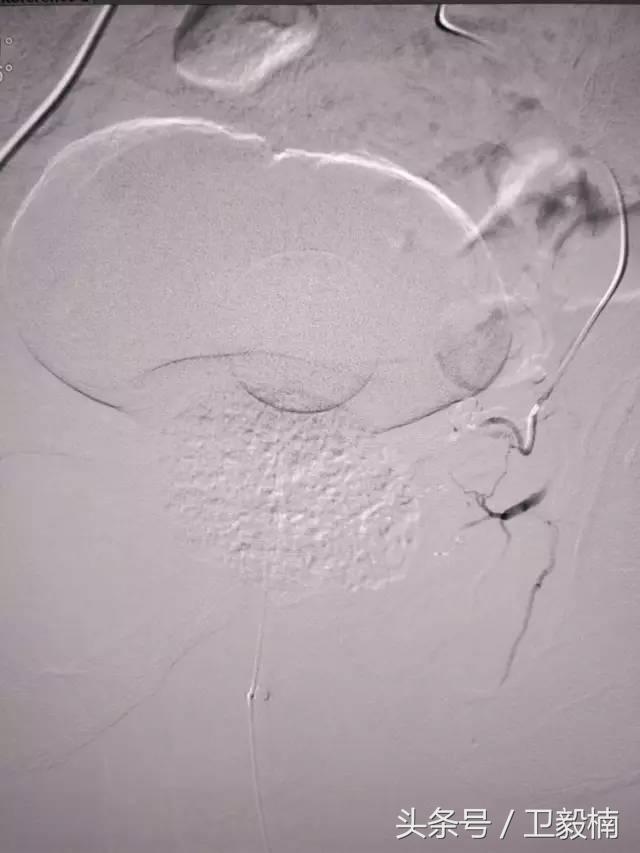

(1)选择性肿瘤供血动脉灌注化疗+栓塞治疗恶性肿瘤。

(3)应用栓塞术治疗海绵状血管瘤,蔓状血管瘤,子宫肌瘤,骨肉瘤,鼻咽部纤维血管瘤等。

七、子宫肌瘤、子宫腺肌症、宫外孕、输卵管阻塞引起的不孕症等妇产科疾病;